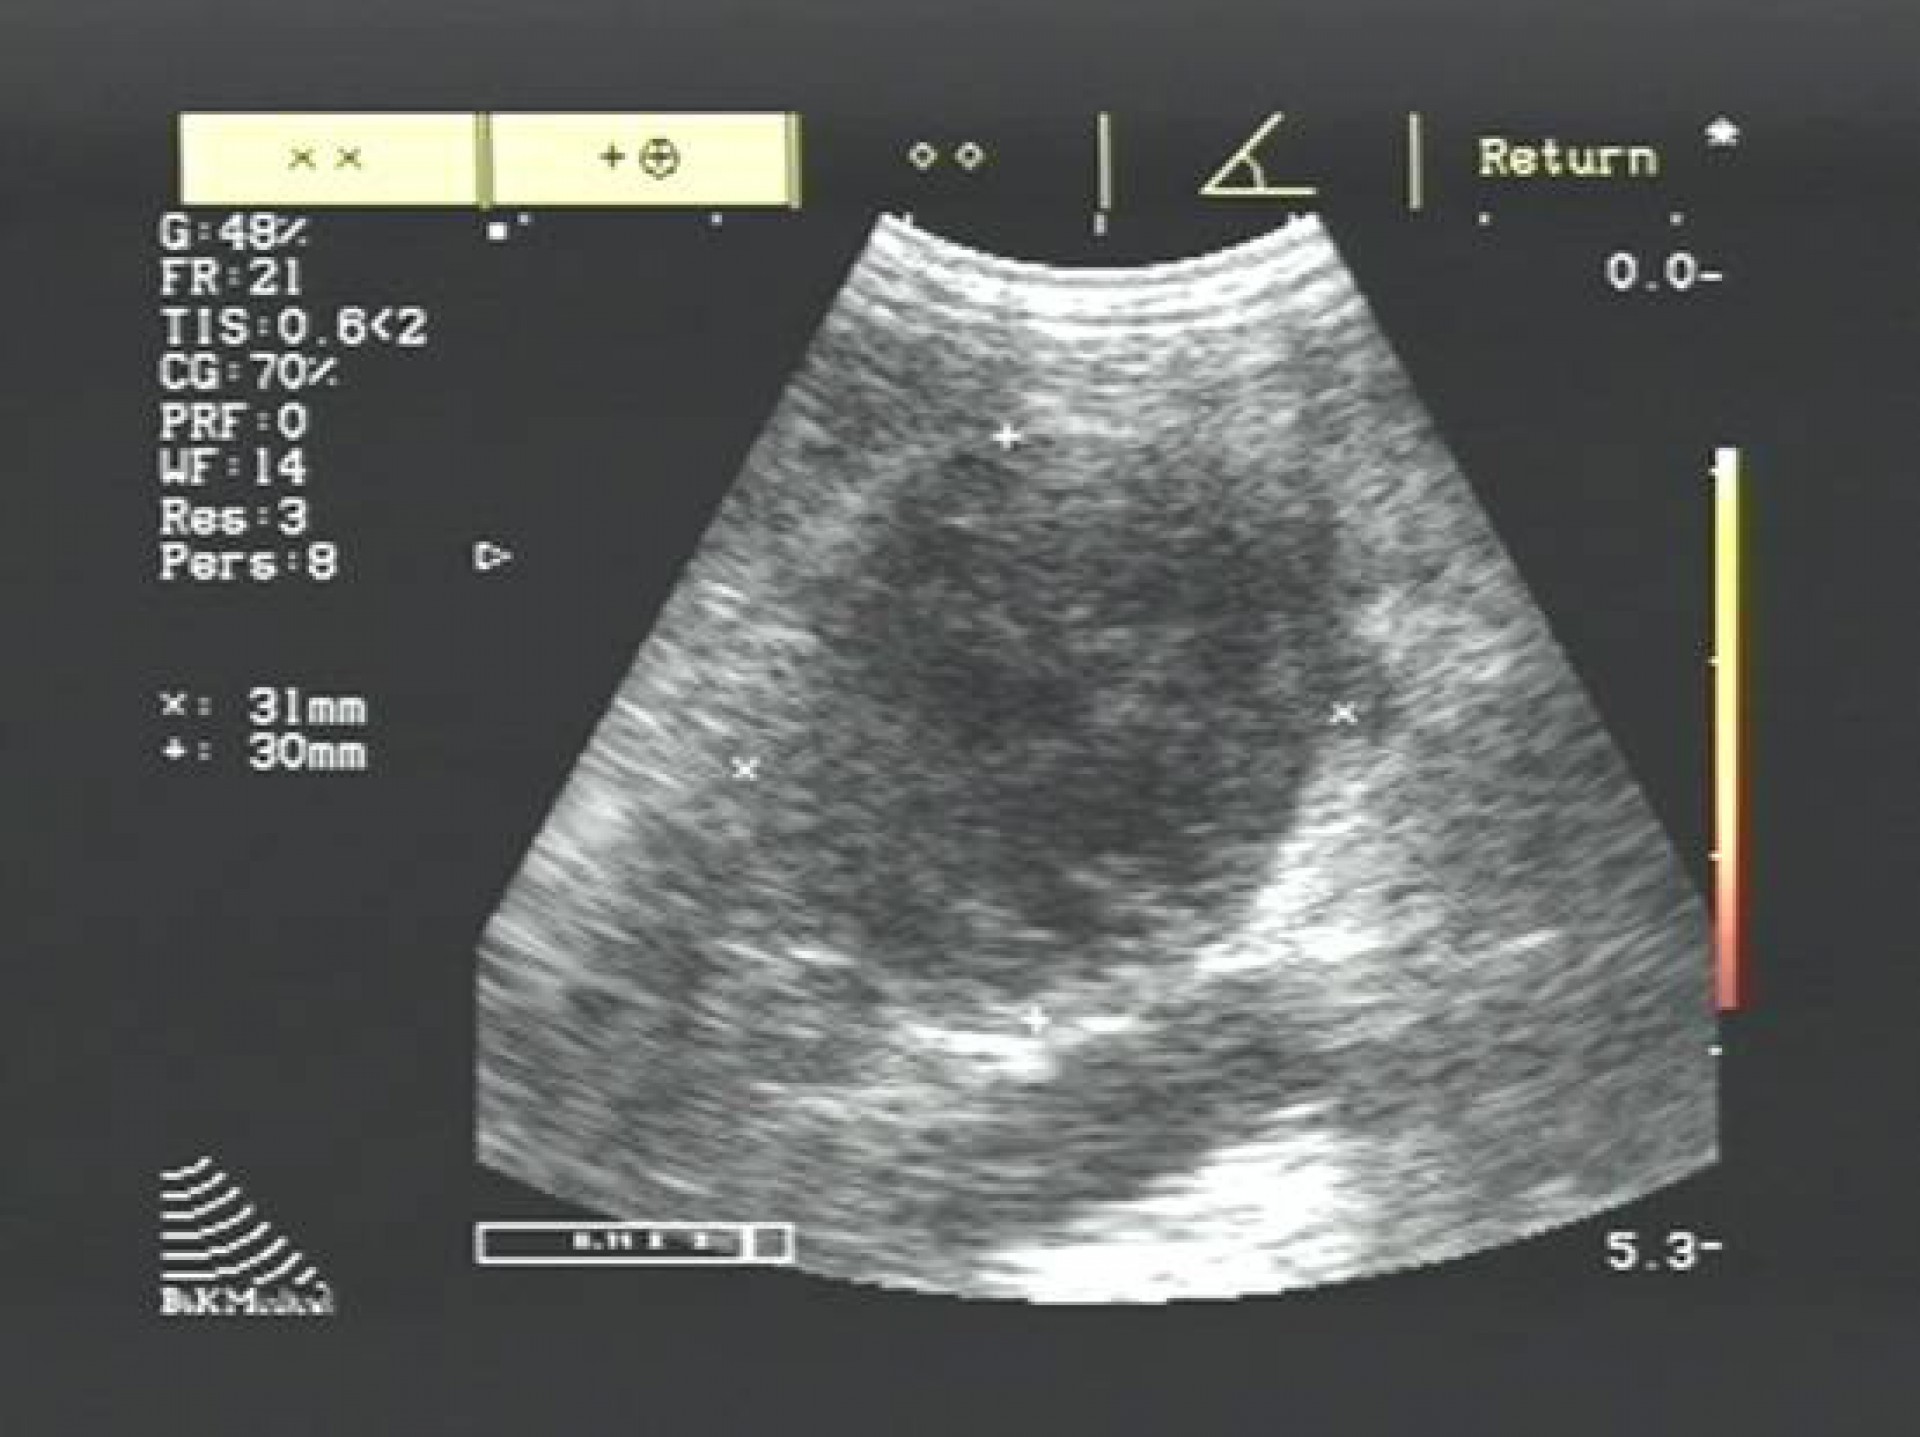

A betegség diagnosztizálása hasüregi ultrahangos vizsgálattal és vérvizsgálattal történik, mely során különös figyelmet kell fordítani a perifériás és centralis forma elkülönítésére.

A daganatos mellékvesét az azonos oldali vese előtti területen a bordaív alatt találjuk meg.